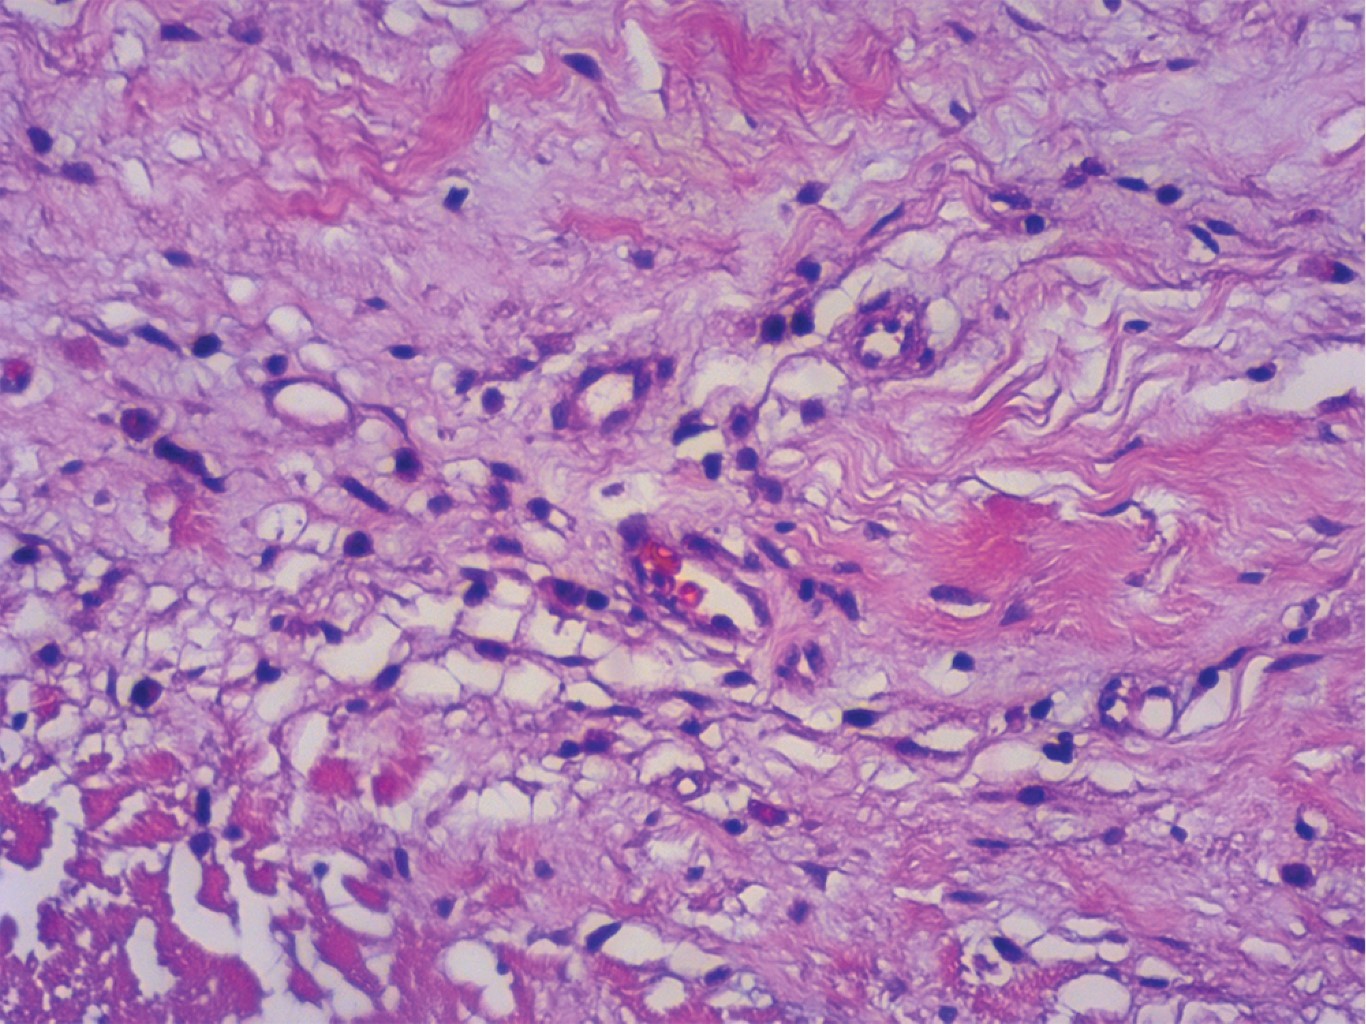

Figura 3